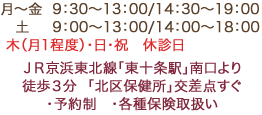

マグネットデンチャー(裏側)

装着前